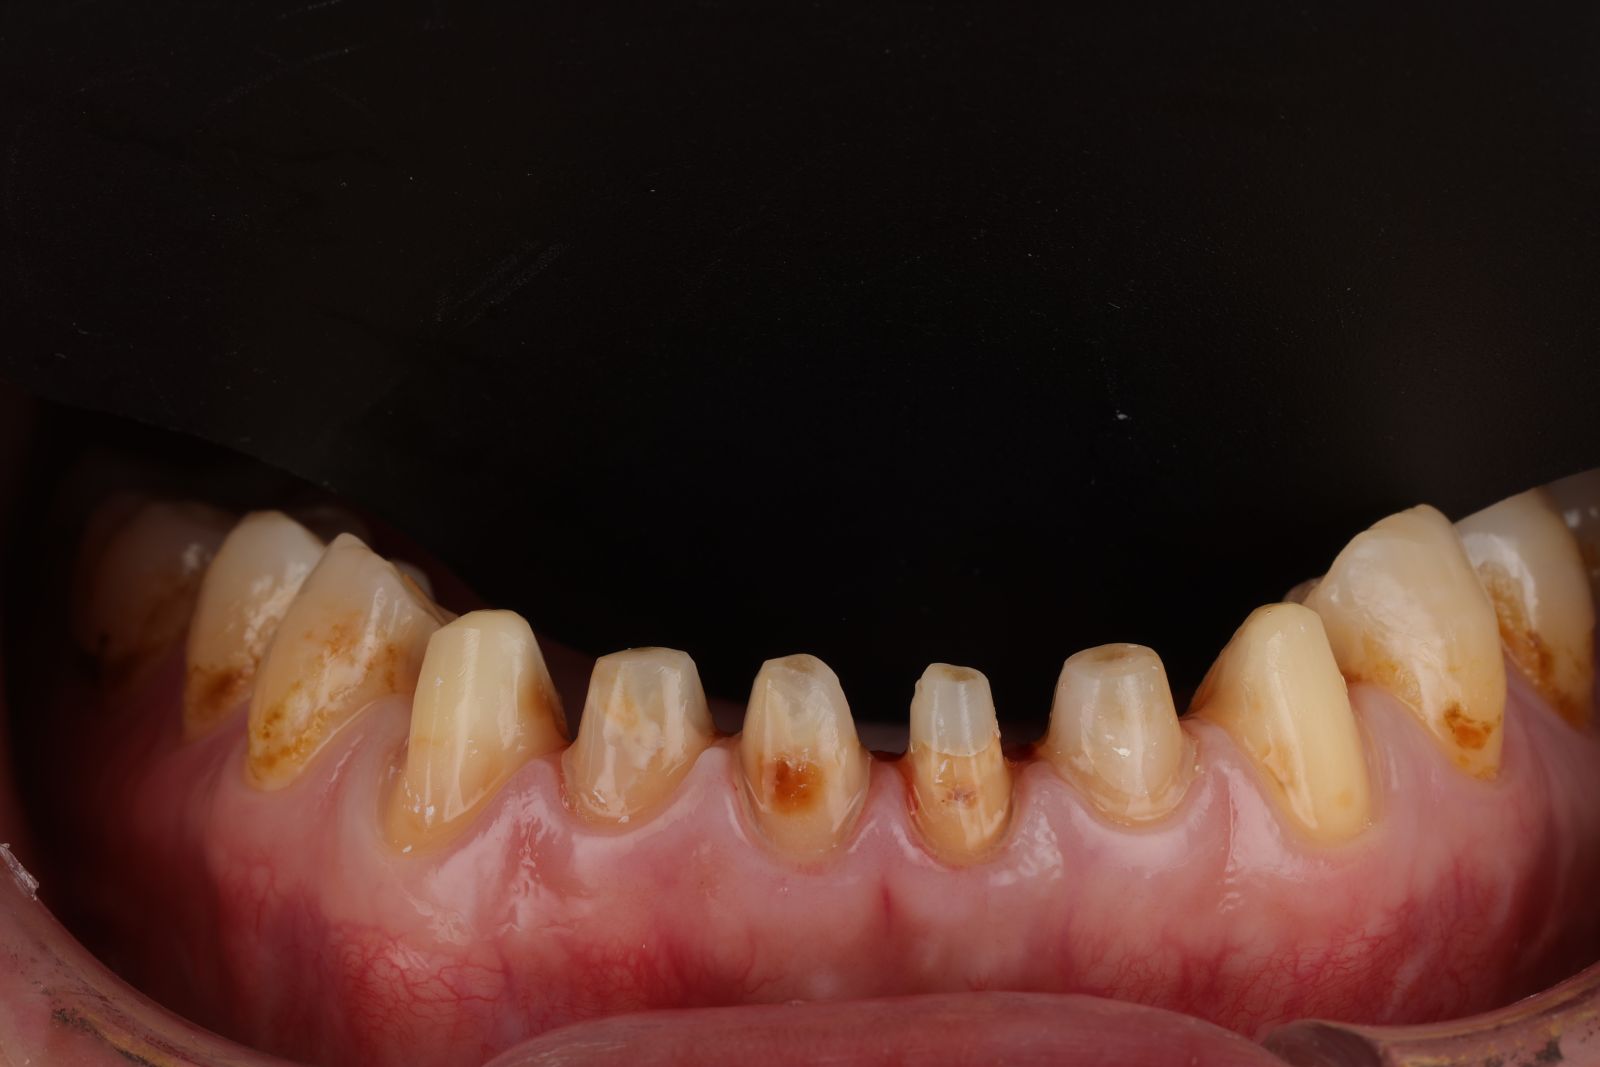

【 案 例 二】

患者因為以前做的金屬假牙邊緣不密合,被金屬染色變黑,以及抽過神經犬齒變色影響美觀。

希望牙齒前牙區能一致變白,型態上也希望能調整得更自然,跟醫生討論之下決定把笑容區6顆牙齒都一起做前牙美學,用全瓷冠搭配美白貼片一起處理!

- 先把舊的假牙拆除後換成臨時假牙,期間先做冷光美白讓牙齒的基礎顏色變白,用保養型冷光美白,讓其他自然牙的部分可以白2~3個色階。一段時間讓顏色穩定後就可以當作正式全瓷冠的顏色參考。